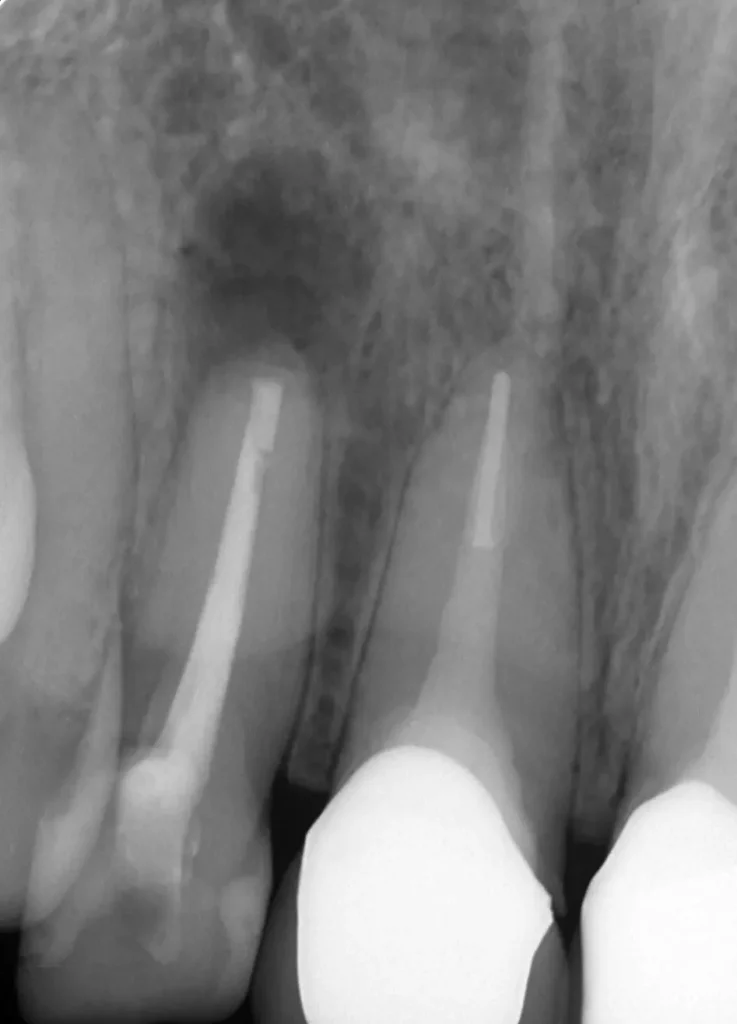

初診時

根の先が黒ずんで炎症があります

術中

症状も消え根の先まで清掃できました

術後

理想的に終了し土台も作製、被せ物は依頼元で行うことになりました